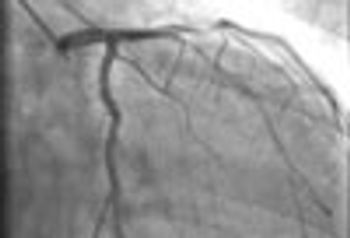

A 72-year-old obese man with chronic atrial fibrillation, hypertension, hyperlipidemia, and a history of tobacco use presented for a routine office visit. A year earlier, he began to experience recurrent chest pain, but an ECG had shown normal T waves.